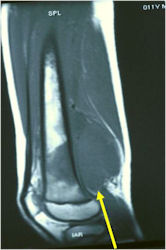

Radiographic Presentation

- Permeative or moth eaten bone destruction

- Ill defined and malignant appearing

- Bony changes are often subtle

- Soft Tissue Mass in 90% of of cases

- Periosteal Reaction in 50% of cases

- Onion Skin (colic pattern of irritation)

- Hair on End (rapid continuous lifting of periosteum)